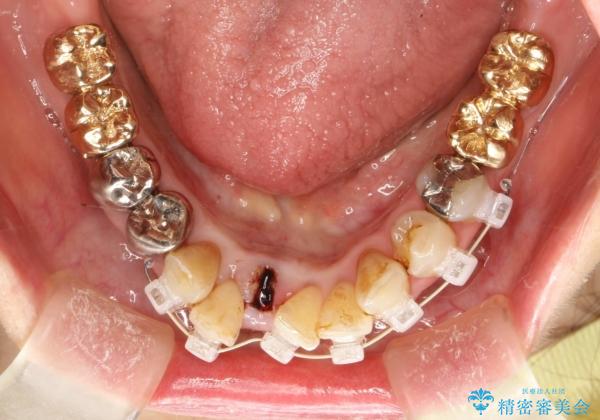

片顎の部分矯正 ワイヤーを用いて短期間でガタつきを改善する

- 歯列から逸脱した歯を1本抜歯し、ワイヤーを用いて短期間で歯列をきれいに整えた。

下顎の歯列を整えることで、上の歯に対して無理な咬み合わせで強い負担がかかることもなくなり、また歯ブラシもしやすくなることで、長期的に良い環境を整えることにつながります。